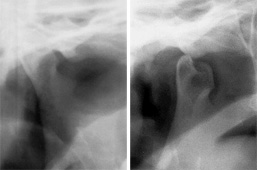

Radiographie tomographique de l’ATM-1

Radiographie tomographique de l’ATM